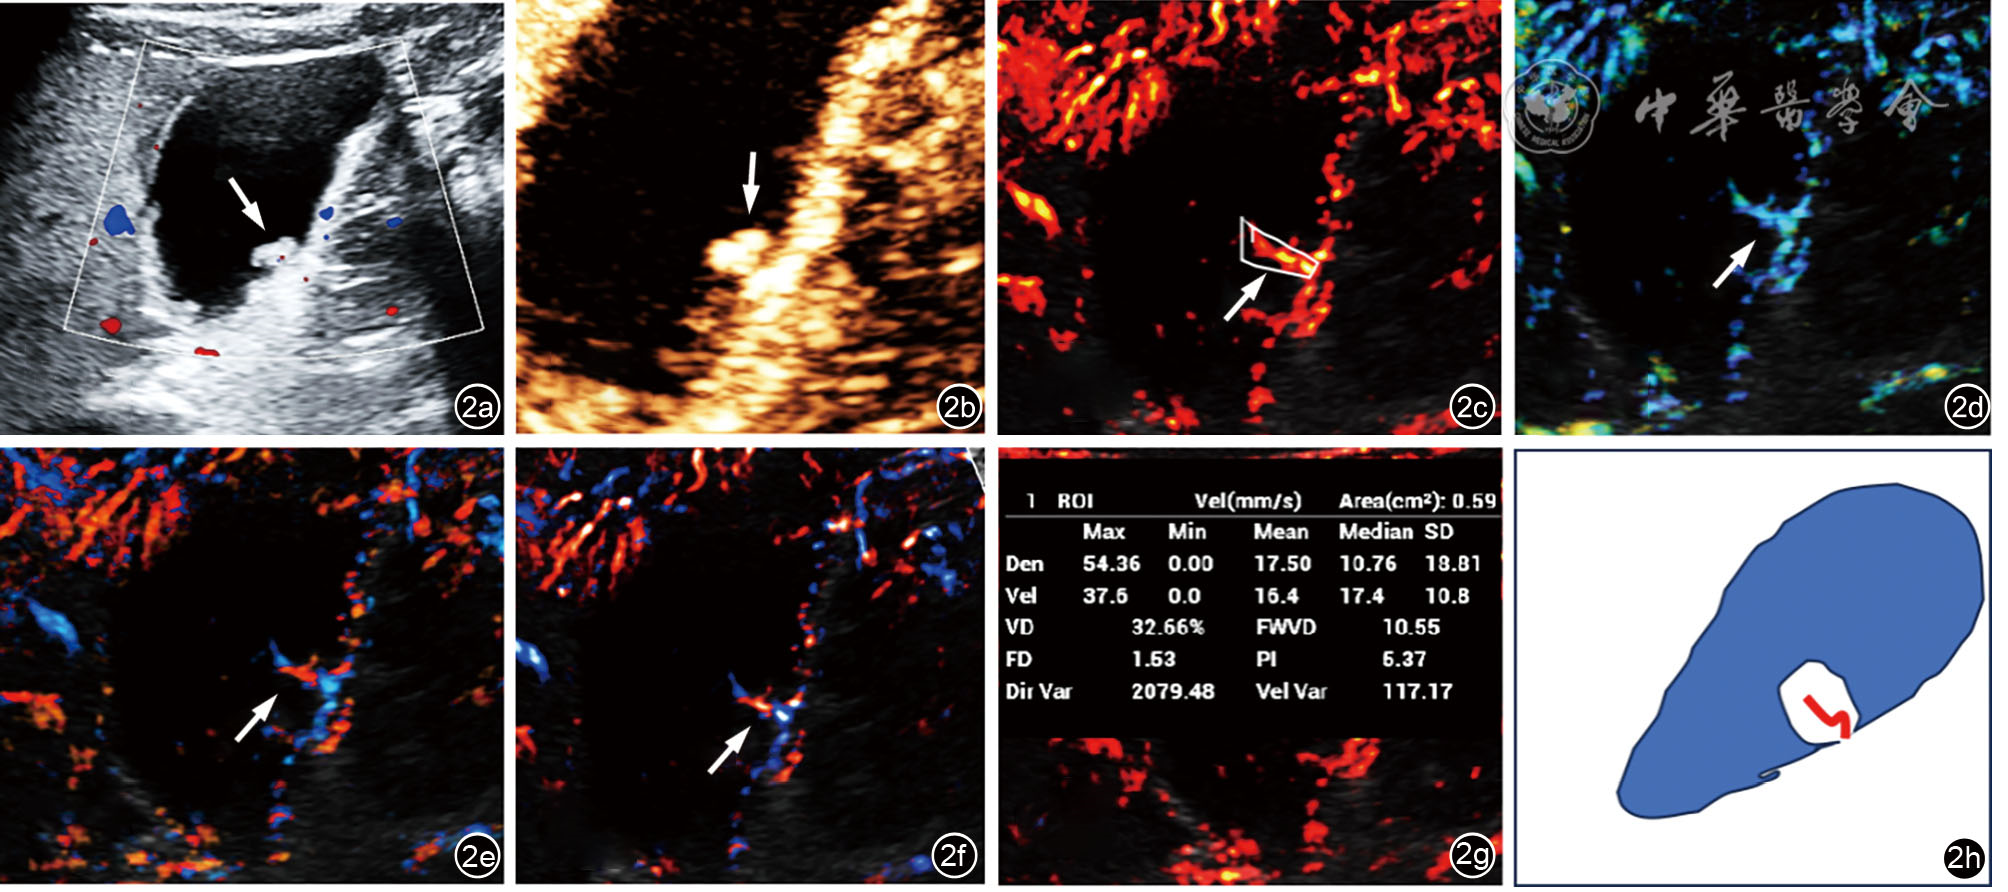

图2 胆囊息肉样病变超声多模态检查(箭头所示为病变处)。图a为常规超声显示胆囊后壁息肉样病变;图b为超声造影显示该病灶静脉期持续增强;图c为超分辨超声显示胆囊息肉内条棒状血流(血管密度图);图d为超分辨超声显示胆囊息肉内条棒状血流(血流速度图);图e为超分辨超声显示胆囊息肉内条棒状血流(血管速度方向图);图f为超分辨超声显示胆囊息肉内条棒状血流(血管密度方向图);图g为超分辨超声对胆囊息肉内血流进行定量分析,获得血流速度(VEL)、血管密度(VD)、血流容积(FWVD)、分形维数(FD)、灌注指数(PI)、方向方差(Dir Var)及速度方差(Ver Var)各定量参数值;图h为示意图显示超分辨超声胆囊肿块血流形态呈条棒状,为Ⅰ型血流模式